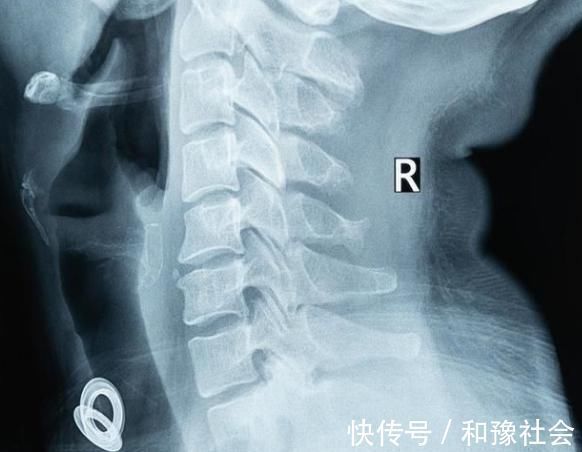

1.颈椎病引起的手部麻醉最常见的类型是神经根型颈椎病,主要由颈突突出的椎间盘增生骨或钙化的韧带和弯曲椎体压迫引起,导致神经传导减弱,导致明显的手部麻醉症状;神经根受压严重后,还容易导致一侧或双侧上肢肌肉无力,甚至肌肉萎缩,严重影响患者的生活质量。一般来说,颈椎病引起的手麻醉在一侧较为常见。